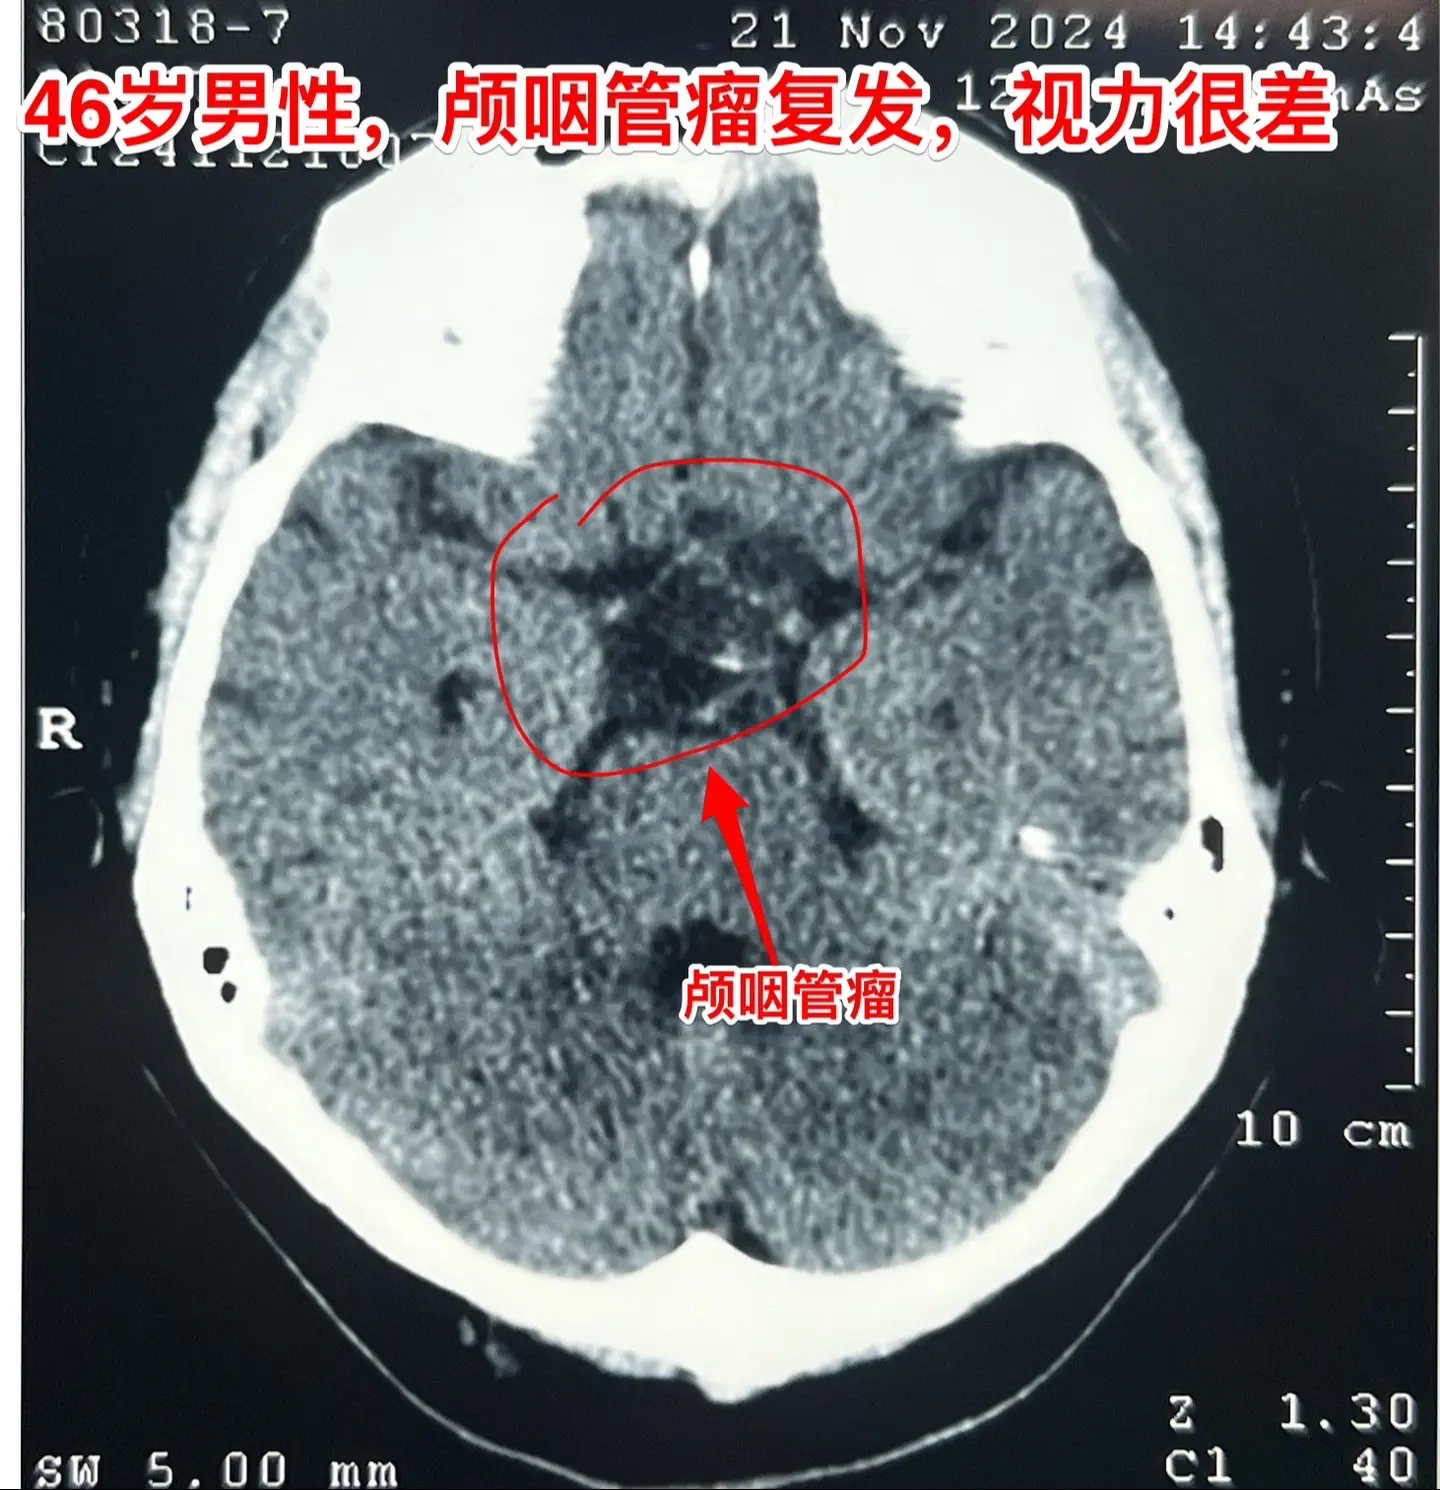

46岁男性两次经鼻手术后再次开颅手术。这是昨日视频中说到的男性病人。 46岁,宜宾市男性,因视力下降发现颅咽管瘤,于2022年8月在外院行经鼻内镜颅咽管瘤切除手术,手术后视力有好转。术后5个月复查磁共振显示肿瘤有复发,一边观察一边采用中药治疗,肿瘤越来越大,左眼失明,右眼视力也很差。不得已于2024.9.24在外院行第二次经鼻手术,手术后左眼视力无好转,右眼 本来就不好的视力也越来越差,病人赶到北京来治疗眼睛,希望能挽救右眼的视力。11月复查磁共振显示肿瘤又长出来了。 已经经鼻手术两次了,距离上次手术时间不到两个月,北京某著名医院的医生不建议再作手术。家属经颅咽管瘤病友推荐找到我,希望再次努力,保住病人的视力。 2024.11.26(周二)我们提前为病人作了手术。术前未曾预料到的是肿瘤得到了完全切除,术后病人右眼的微弱视力还是保住了。等出院后可以作高压氧舱治疗,提升视力,争取能达到生活自理的效果。